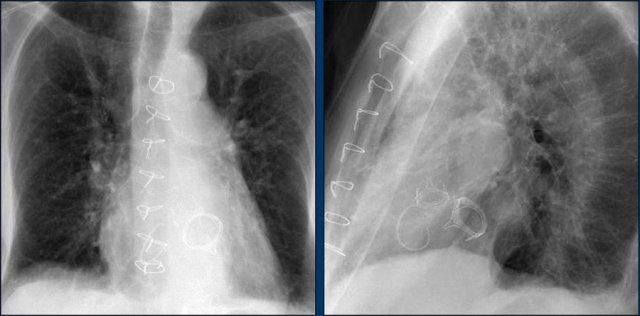

Các phát hiện bao gồm:

- Hai điện cực thượng tâm mạc kết nối với máy tạo nhịp

- ICD

- Hai điện cực đến mỏm thất phải

- Một điện cực chứa hai cuộn sốc điện

- Van ba lá (mũi tên)

- Van hai lá

Bệnh nhân này đã được sửa chữa ba van:

- Van ba lá

- Van động mạch chủ

Có máy tạo nhịp tim với điện cực thượng tâm mạc.

Phương án này được lựa chọn vì người ta cho rằng điện cực đặt theo đường thông thường vào thất phải sẽ ảnh hưởng quá nhiều đến chức năng của van ba lá nhân tạo.

Mũi tên trắng chỉ vào van động mạch chủ.

Mũi tên vàng chỉ vào van hai lá.